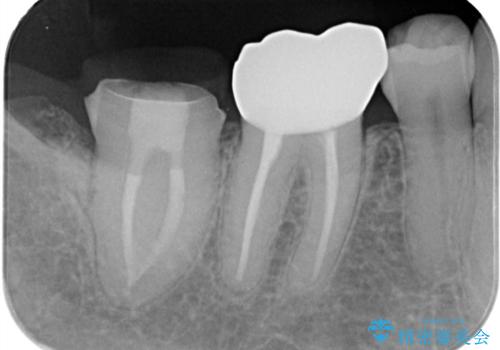

- 冷たいもので長引く痛みがあることを主訴に来院されました。

抜髄を行い、オールセラミッククラウンにて修復を行いました。

根管充填はバイオセラミックシーラーを使用しています。